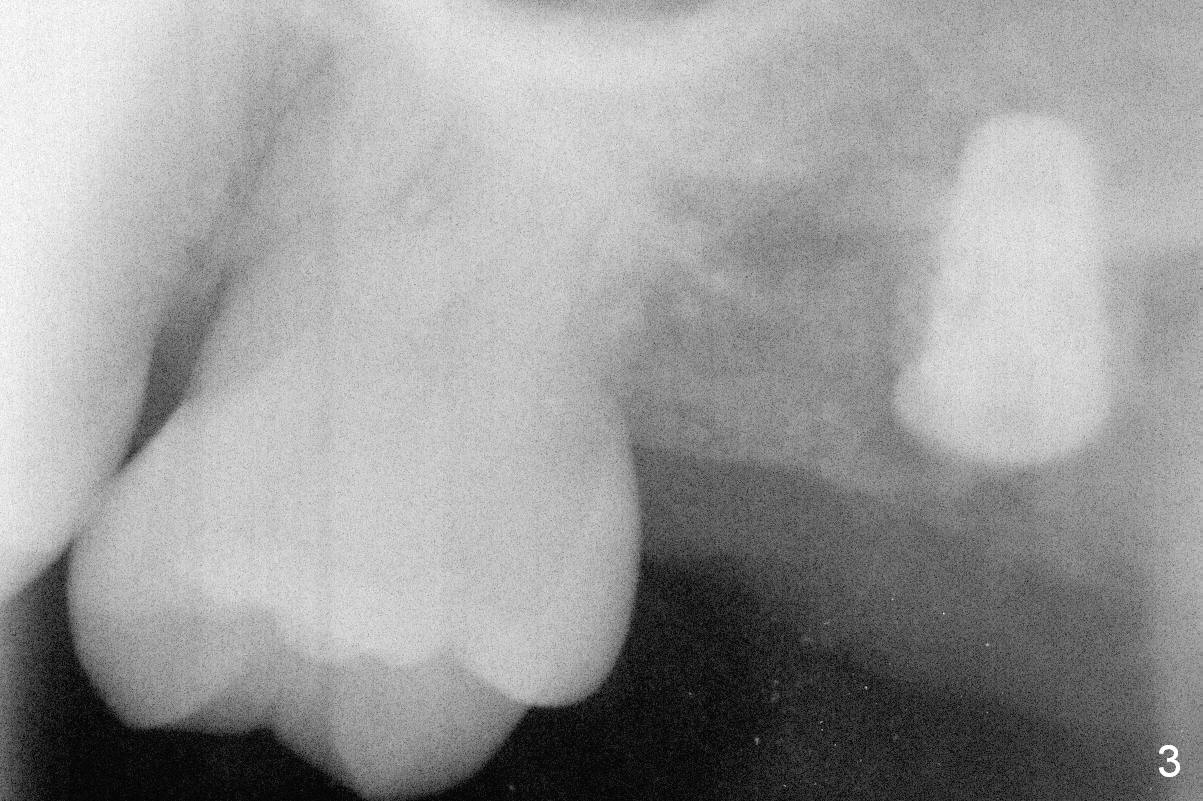

Initial osteotomy at the site of #15 for 4x11 mm dummy implant is created by #15 blade, Magic Split and Magic Expanders (ME) 3.0 and 3.8 mm (flapless, Fig.1,2, 4A (blue circle)). The implant is palatally displaced. Release incision confirms the deviation. A new osteotomy is established with 1.6 mm pilot drill in the middle of the site (Fig.4A (occlusal view) red circle). Distal to the new osteotomy is the incompletely healed socket (brown circle). As the osteotomy is enlarged by ME until 4.3 mm and placement of 4.5 and 5.0 mm dummy implant and of 5.5x9 mm definitive one (Fig.3, 4B large red circle), the osteotomy gradually deviates distopalatally. Introspectively, the new osteotomy should have been placed more buccomesially (Fig.4C red circle) so that the final osteotomy may end up normally (Fig.4D large red circle).